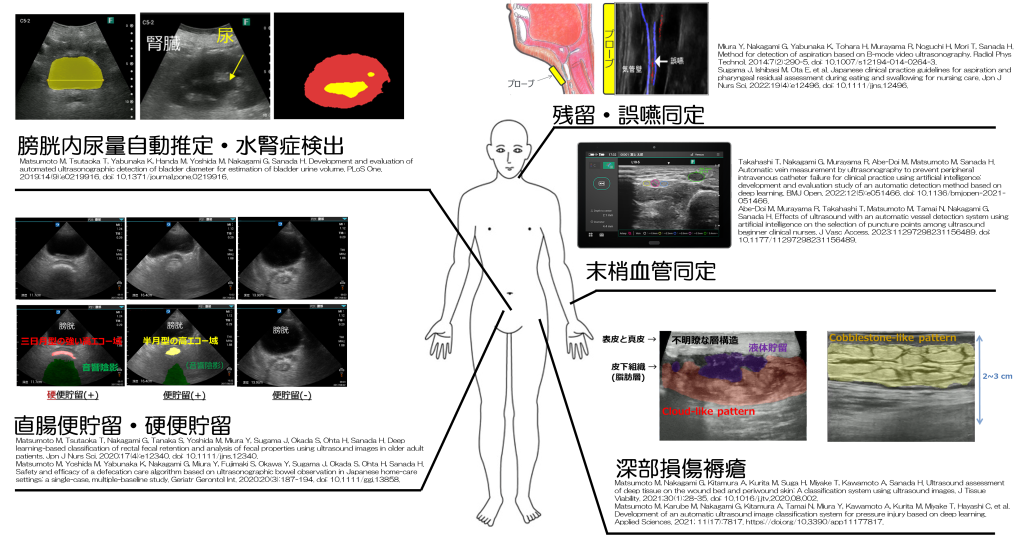

看護を変える新しいフィジカルアセスメント

―エコー(超音波)を活用した DX 時代の看護実践と教育―

近年、看護の現場では 患者の状態を「より正確に」「より負担なく」「その場で」把握することがこれまで以上に求められています。高齢化が進む日本において、排尿・排便、循環、嚥下、褥瘡などのケアはますます複雑化し、従来の視診・触診・聴診・打診・問診だけでは判断が難しい場面が増えています。

こうした課題を解決する新たなフィジカルアセスメントとして注目されているのが、エコー(超音波)を用いた看護アセスメントです。

エコーが看護を変える理由:見えなかった身体内部を「リアルタイムに可視化」する

エコーは、身体に超音波を当てて反射を画像化する技術です。

痛みも侵襲もなく、その場で結果が分かるため、ベッドサイドでの迅速な判断が可能です。

• 膀胱内の尿量

• 直腸内の便貯留

• 血管の走行・太さ

• 褥瘡の深さや組織の状態

• 誤嚥の有無

など、従来は経験や推測に頼ってきた情報が、客観的な画像として確認できるようになります。

AI による読影サポートで初心者でも安心

当研究チームは、企業と連携し、エコー画像をAIによって分析して異常領域に自動着色する技術を開発しました。

これにより、初心者でも血管や膀胱、便塊などを迷わず判断でき、正確な看護判断の実現を後押ししています。これまで研究・教育で標準化してきた“看護に使えるエコー”の代表例をご紹介します。

1. 排尿アセスメント

残尿量の測定や尿閉の評価、水腎症の早期発見など、排尿ケアに欠かせない情報が得られます。

2. 排便アセスメント

直腸内の便貯留を分類し、適切な摘便・緩下剤・排便ケアにつなげられます。AI による便性状の推定も可能です。

3. 嚥下アセスメント

誤嚥のリアルタイム検出や咽頭残留の把握が、エコーで非侵襲的に行えます。

4. 末梢静脈カテーテル・点滴

血管の深さ・太さ・圧迫での虚脱を確認し、失敗を減らす穿刺部位選択ができます。AI による血管自動計測機能も実装済みです。

5. 褥瘡アセスメント

皮下組織の損傷や深部損傷褥瘡(DTI)の早期発見、創周囲組織の変化を客観的に評価できます。